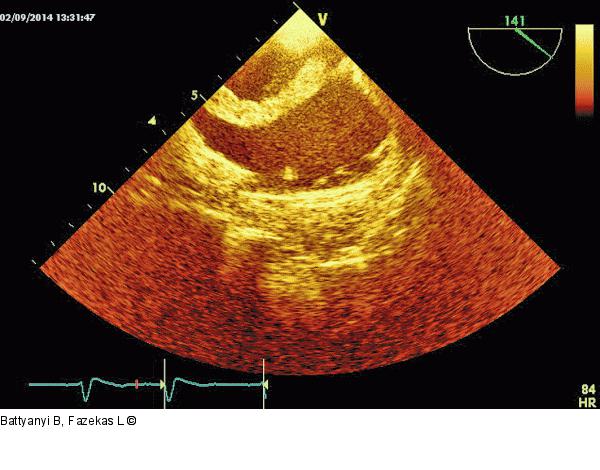

Abbildung 6: Thromboembolus Wie Abb. 5, jedoch aus einer weiter gedrehten Position. Gut zu sehen ist der homogene, gut geformte Abschnitt des Gerinnsels. |

Wie Abb. 5, jedoch aus einer weiter gedrehten Position. Gut zu sehen ist der homogene, gut geformte Abschnitt des Gerinnsels. |